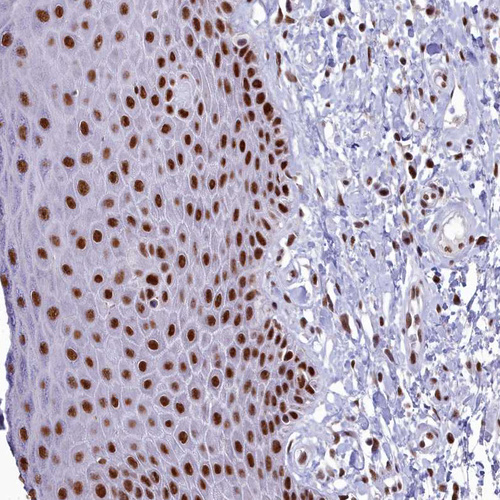

Immunohistochemical staining of human lymphoid tissues shows strong nuclear positivity in non-germinal center cells.